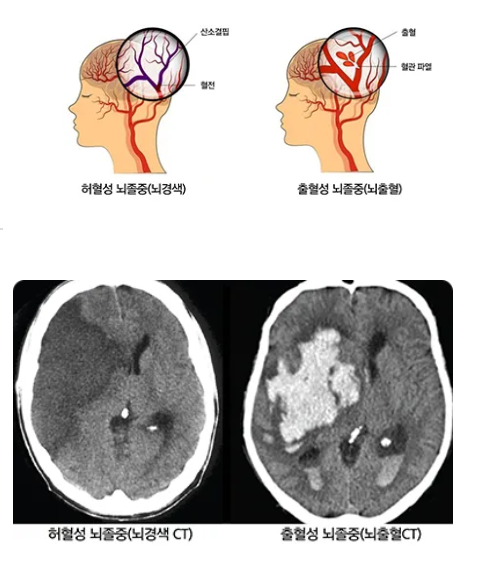

뇌졸중이란 뇌에 혈액을 공급하는 혈관이 갑자기 막히거나(허혈성 뇌졸중), 터지면서(출혈성 뇌졸중) 뇌에 손상이 생기는 질환입니다.

뇌졸중은 크게 두 가지 유형으로 나뉩니다.

첫 번째는 혈관이 막히는 경우입니다.

혈관이 막혀 공급받던 뇌의 일부가 손상되는 상태를 '뇌경색'(허혈성 뇌졸중)이라고 하며, 서양에서는 주로 이 유형이 많습니다.

두 번째는 뇌혈관이 터지는 경우입니다.

터진 혈관에서 피가 고여 뇌에 손상을 입히는 상태를 '뇌출혈'(출혈성 뇌졸중)이라고 합니다. 우리나라에서도 허혈성 뇌졸중이 발생 빈도가 약 85%로 출혈성 뇌졸중보다 더 흔하다고 알려져 있습니다.

뇌졸중은 정확한 진단과 빠른 조치를 통해 치료 효과를 극대화할 수 있습니다. 일반적으로 전산화 단층촬영(CT), 자기공명영상(MRI)과 같은 영상 진단을 시행하여 환자의 뇌 상태를 확인하게 됩니다. 경우에 따라 뇌 혈류량 검사나 혈관 검사를 통해 뇌혈관 상태를 추가로 확인하기도 합니다.